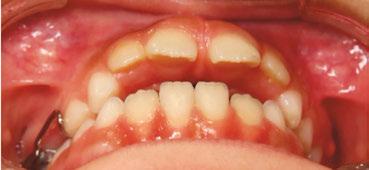

An 8-year-old Hispanic male presented to our private practice in Miami, Florida with the chief complaint of a missing front tooth (Figure 1). Upon review of his medical history, the mother revealed that her son had Autism Spectrum Disorder and confirmed that his condition was severe. This patient did not take

12 Orthodontic Practice US Volume 14 Number 2 CLINICAL

Figure 1: Face of 8-year-old patient at initial consultation

any medications, was nonverbal, avoided eye contact with any staff member including the treating pediatric dentist, did not sit in the dental chair, and was constantly tapping his ears. No dental radiographs were obtained due to his uncooperative behavior. For the dental exam, the mother agreed and consented with placing him in a passive restraining device. With a limited visualization of his oral cavity, a mixed dentition was noted. The maxillary right permanent central incisor was absent. No significant pathology was found in his oral soft tissues. Dental caries was found on both primary and permanent molars. A decision was made to complete dental treatment using general anesthesia as a behavior management technique at the local children’s hospital.